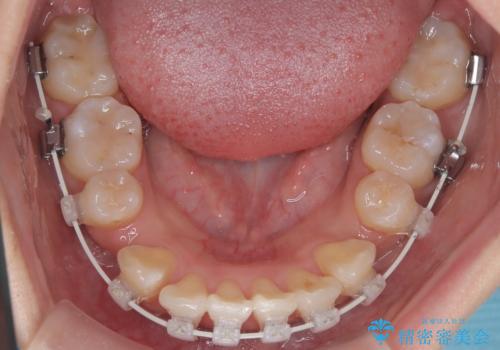

今回の矯正治療では、まず計画通り上下左右の小臼歯4本を抜歯し、八重歯や正中のズレを解消するための十分なスペースを確保しました。装置には、目立ちにくい白いブラケットとワイヤーを使用した審美ワイヤー矯正を採用。

抜歯によってできたスペースを利用し、

八重歯: 突出していた八重歯を歯列内に誘導し、デコボコを解消しました。

正中のズレ: 歯を左右対称に移動させることで、上下の歯の中心線を正確に合わせ、顔全体のバランスも改善しました。